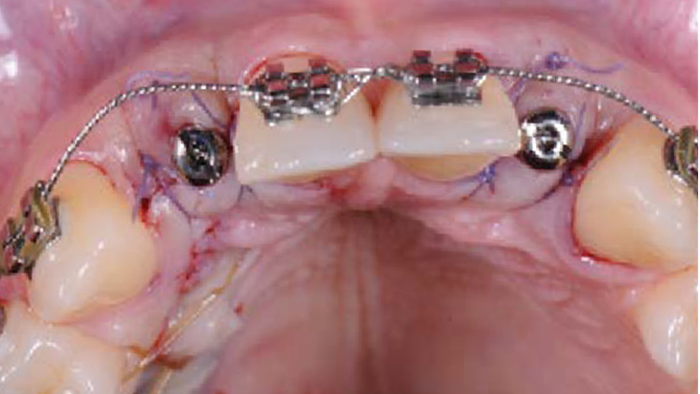

Clinical case: 3.0 mm MiNi implants placement at #12, #22

- Courtesy of Dr. Achraf Souayah, Tunise -

Keywords

Anterior esthetics, MiNi, flap elevation, minimally invasive technique, soft tissue management, esthetic zone, Dr. Achraf Souayah, anterior aesthetics, aesthetic, aesthetics, esthetic, #12, #22

Products:

MiNi implant system